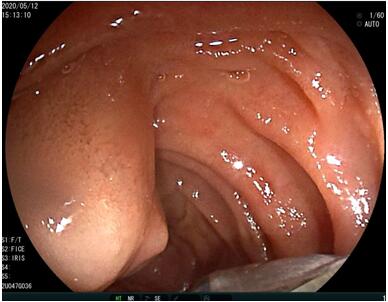

69歲王姓患者,因“發(fā)現(xiàn)無(wú)痛性黃疸1月”入院,根據(jù)患者病史,患者診斷傾向于壺腹部腫瘤所致梗阻性黃疸。予以完善腹部CT及上腹部MRI加MRCP均顯示肝內(nèi)外膽管擴(kuò)張,未發(fā)現(xiàn)明顯膽管,胰腺及十二指腸乳頭部腫瘤,且患者CA199正常。以前醫(yī)院未引進(jìn)超聲內(nèi)鏡,這類(lèi)患者到此就遇到診斷瓶頸。此患者經(jīng)過(guò)消化內(nèi)科張丹霞副主任醫(yī)師完善超聲內(nèi)鏡檢查后,可以清楚顯示膽總管下段壁內(nèi)軟組織占位。患者通過(guò)超聲內(nèi)鏡檢查診斷明確,轉(zhuǎn)至肝膽外科行手術(shù)治療。

超聲胃鏡圖片